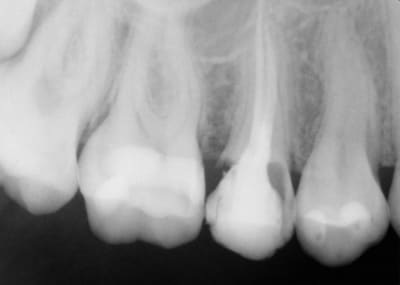

J'ai dévitalisé la 15 il y a environ un mois car douloureuse en sachant qu'elle n'irait pas bien loin et effectivement la paroi palatine s'est fracturée.

Je suis sous gingival, probablement juxta osseux et probablement carié en palatin, IC et céram inenvisageables en l'état.

Moi ce qui m'interpelle le plus en dehors de l'ortho qui te rends une gamine de 15 ans dans cette état carieux sur 14/15/16 , c'est le pourquoi du comment . Elle est sponso par Haribo ou Cola la môme ?

A quoi cela sert de se tordre le coup pour la 15 , quand la 16 ( apriori à la vue de la Z , gros compo sur le collet ) va y passer dans 2 ans et bientot la 17 qui vient juste de naitre .

la 14 ok, 2 petits soins...

la 16 amha c'est plutôt un reste de colle ou de ciment ODF qui servait au scellement de la bague...

2 soins sur la 14 , la 15 délabrée et surement un soin sur le sillon disto-palatin de 16 ;o)))

Effectivement, état déplorable après plus de 4 ans d'odf.

La 16 c'est un gros pâté de composite qui est en palatin, ML sur quasi toute la face de la dent , je ne sais pas encore ce qui est dessous.